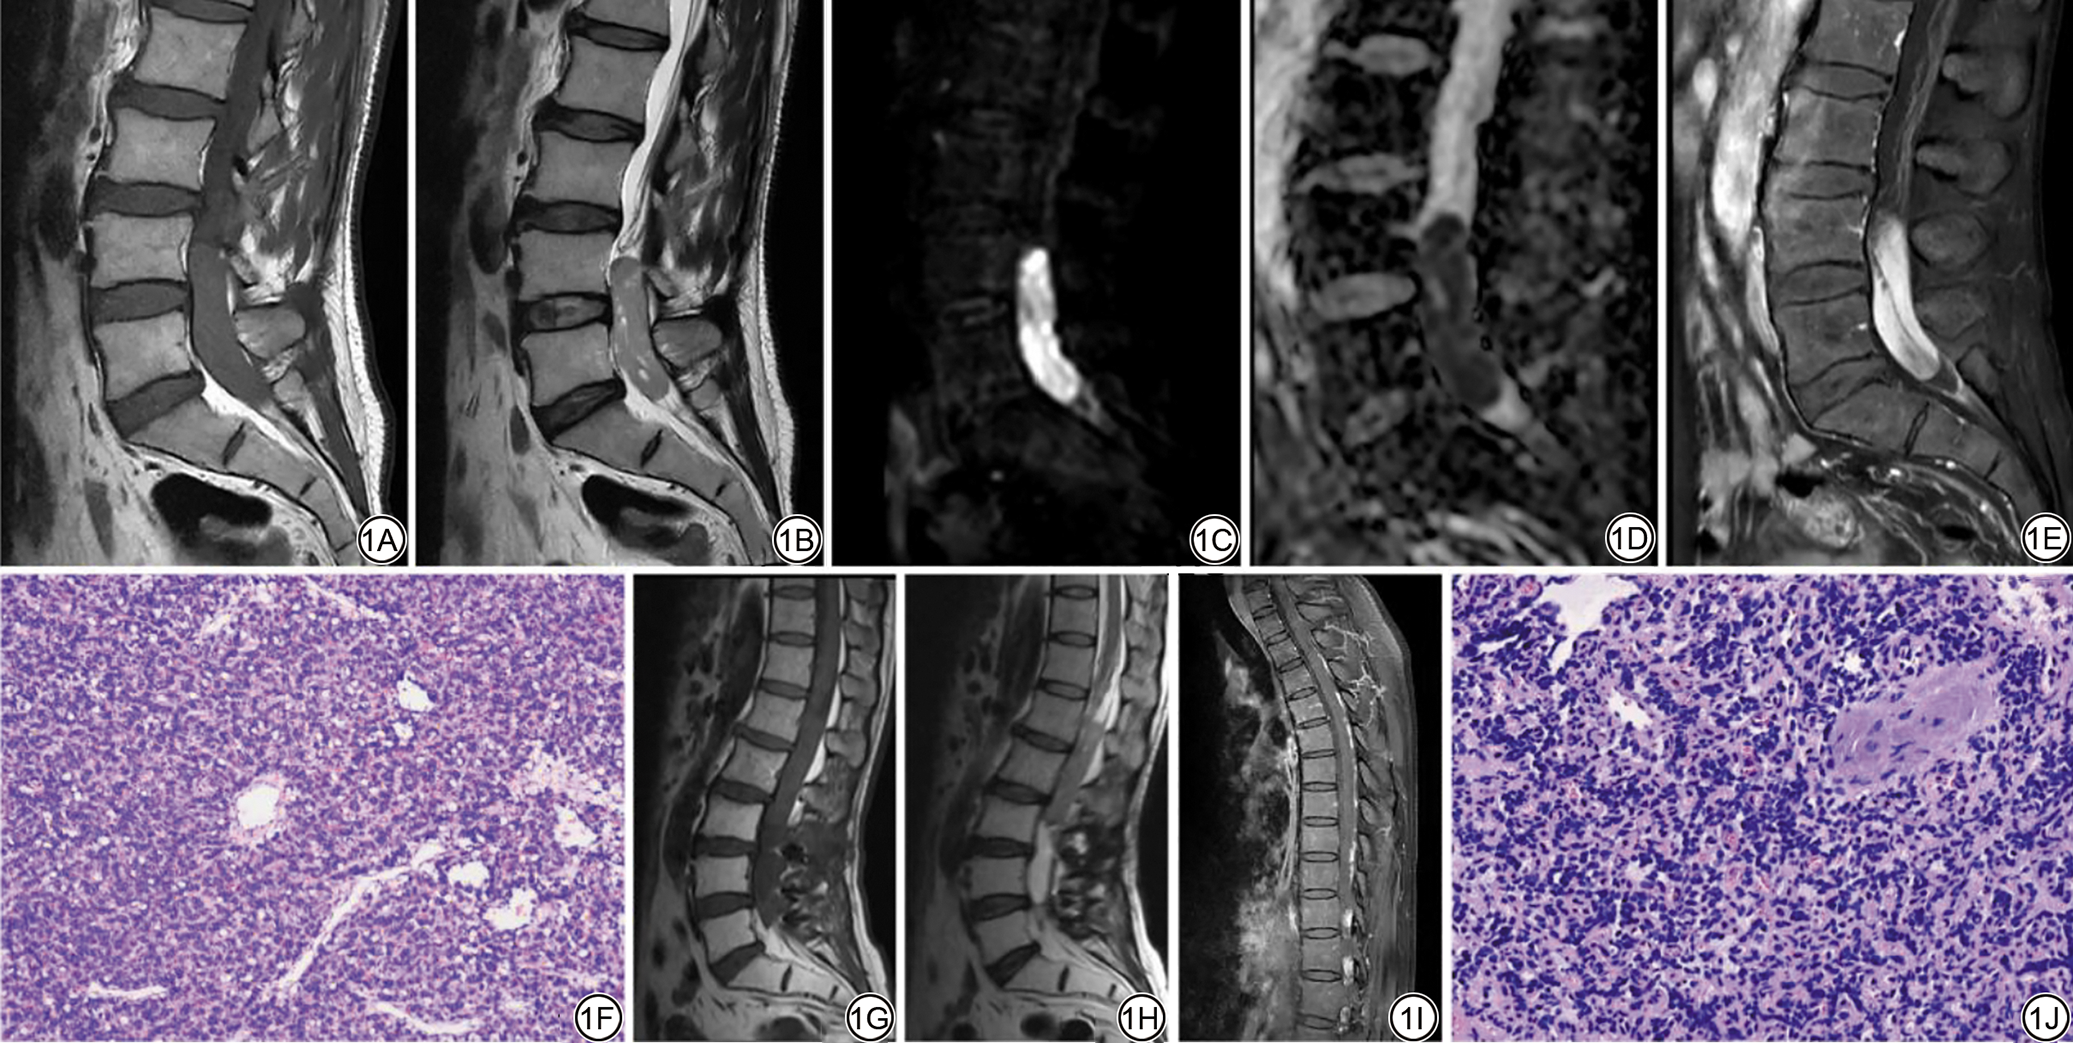

患者男,51岁,因“臀部及下肢疼痛麻木2月”于2022年3月就诊于我院,患者于2个月前无明显原因及诱因下出现臀部及下肢疼痛,主要表现为右侧臀部及右侧大腿根部疼痛、行走困难、腰部活动受限伴下肢麻木。查体:直腿抬高试验阳性,双下肢近端肌力5级,四肢肌张力正常。实验室检查未见明显异常。腰椎MRI平扫+增强示:腰4-骶1椎体水平硬脊膜囊内见类椭圆形T1WI等信号、T2WI(图1A~1B)及脂肪抑制T2加权成像(T2-weighted imaging with fat saturation, T2WI-FS)稍高信号影,大小约17 mm×13 mm×57 mm,其内可见多发小囊状T1WI等信号、T2WI及T2WI-FS高信号影,扩散加权成像(diffusion weighted imaging, DWI)及表观扩散系数(apparent diffusion coefficient, ADC)显示弥散受限(图1C~1D),增强扫描呈明显较均匀强化,内见条状低信号无强化影(图1E),侵犯马尾神经。

患者于2022年4月收住院,4日后患者经评估无手术禁忌后,在全麻下行“椎管内肿瘤切除术+椎管成形术”。术后病理显示肿瘤细胞密度较高,胞核大小不一,染色质结构相对致密均匀,排列呈条索状,可见核分裂象,血管丰富,考虑为恶性肿瘤(图1F)。免疫组化:Ki-67(40%+)、Syn(+)、Fli-1(+)、CD56(+)、NSE(-)、CgA(-);肿瘤细胞EMA、D2-40、GFAP、Olig-2、SOX-10、CK、S100、CAM5.2、Vimentin、ERG均阴性;网状纤维染色(+)。经会诊:(椎管)小圆细胞恶性肿瘤,结合免疫组化,符合神经母细胞瘤。

术后1年患者因“臀部及左下肢疼痛麻木5天”再次就诊。行腰椎MRI平扫示:胸11-腰3水平椎管内见条片状T1WI低信号T2WI略高信号灶(图1G~1H),截面约71 mm×13 mm。腰椎/胸椎增强MRI示:胸腰骶椎较长水平椎管内见弥漫性异常信号,约累及胸2-骶2水平,部分区域沿硬脊膜走行,见不规则条片状、团块状T1WI增强扫描明显强化影(图1I),DWI呈扩散受限高信号影,病变主体位于胸12-腰3水平,病变局部充填椎管,侵犯脊髓圆锥及马尾神经,明显不均匀强化。患者入院后再次行“椎管内外病灶切除术”,术后病理:(椎管内占位肿瘤)小圆细胞恶性肿瘤(图1J),免疫组化支持神经母细胞瘤或原始神经外胚层肿瘤。指标如下:CK(-)、LCA(-)、Syn(-)、CgA(-)、PGP9.5(-)、CD56(+)、GFAP(-)、Neu-N(-)、NF(-)、c-myc(-)、ALK(-)、Desmin(+)、CD99(+)、NKX2.2(+)、NSE(-)、NKX3.1(-)、Fli-1(+)、ERG(+)、Ki-67(+40%~50%)。术后病理支持椎管内神经母细胞瘤复发并转移。术后每3个月随访一次,其间未见肿瘤复发,最后一次随访时间为2024年4月。

图1  男,53岁,椎管内神经母细胞瘤。1A~1B:MRI示腰4-骶1椎体水平硬脊膜囊内见类椭圆形T1WI等信号、T2WI稍高信号影,其内可见多发小囊状T1WI等信号、T2WI高信号影;1C~1D:扩散加权成像序列显示病灶呈高信号,对应的表观扩散系数图呈低信号,提示病灶弥散受限;1E:增强扫描T1WI示病变呈明显较均匀强化,内见条状低信号无强化影;1F:病理图(HE ×200)可见肿瘤细胞密度较高,胞核大小不一,染色质结构相对致密且均匀,排列呈条索状,可见核分裂象,血管丰富;1G~1H:术后复发腰椎MRI示胸11-腰3水平椎管内见条片状T1WI低信号T2WI略高信号;1I:复发后胸椎增强扫描T1WI示椎管内见弥漫性异常信号,见不规则条片状明显强化影;1J:病理图(HE ×400)符合小圆细胞恶性肿瘤。

Fig. 1  Male, 53-year-old, intraspinal neuroblastoma. 1A, 1B: MRI shows oval T1WI equal signal and T2WI slightly high signal in the dural sac at the level of lumbar 4-sacral 1 vertebral body. Multiple small cystic T1WI equal signal and T2WI high signal were seen in the dural sac. 1C, 1D: Diffusion-weighted imaging shows high signal intensity, and the corresponding apparent diffusion coefficient map shows low signal intensity, indicating restricted water diffusion within the lesion. 1E: Enhanced scan T1WI shows that the lesion is significantly homogeneously enhanced, and there is a strip of low signal without enhancement. 1F: The pathological diagram (HE ×200) shows that the tumor cell density is high, the nucleus size is different, the chromatin structure is relatively dense and uniform, the arrangement is cord-like, the mitotic image is visible, and the blood vessels are rich. 1G, 1H: Postoperative recurrence of lumbar MRI shows thoracic 11-lumbar 3 level spinal canal see strip patchy T1WI low signal T2WI slightly high signal T1WI low signal T2WI slightly high signal. 1I: T1WI enhanced scan of the thoracic spine after recurrence shows diffuse abnormal signals in the spinal canal, and irregular flakes of obvious enhancement are seen. 1J: The pathological diagram (HE ×400) is consistent with small round cell malignant tumor.